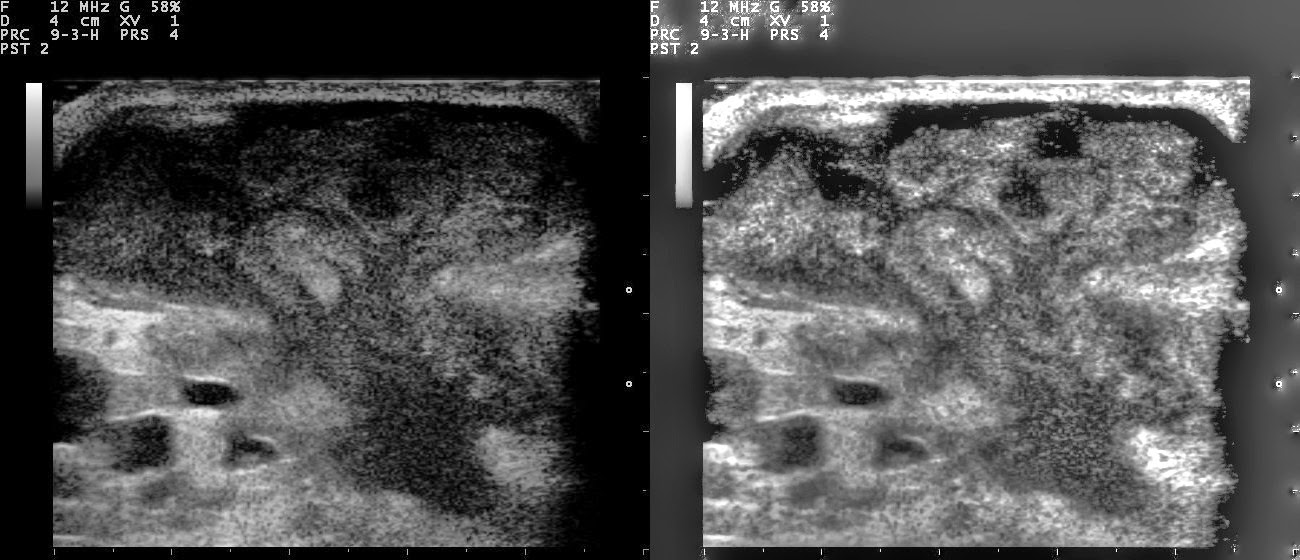

Las microcalcificaciones son acumulaciones diminutas de calcio dentro del tejido mamario, generalmente menores a 0.5 milímetros. Son detectables únicamente mediante estudios de imagen como la mastografía, ya que no se pueden palpar ni producen síntomas visibles. Su presencia no siempre indica un problema grave; muchas veces están asociadas a cambios benignos como quistes, fibroadenomas, cicatrices o procesos inflamatorios.

El radiólogo clasifica las microcalcificaciones según su forma, tamaño, distribución y patrón. Las benignas suelen ser redondeadas, dispersas y uniformes, mientras que las que requieren mayor vigilancia pueden ser pleomórficas (de diferentes formas y tamaños), agrupadas o con distribución lineal segmentaria.

Cuando las microcalcificaciones generan sospecha, el médico puede solicitar estudios complementarios. Uno de ellos es la mastografía con magnificación, que permite observar los detalles del patrón de las calcificaciones. Si el riesgo es moderado o alto, el siguiente paso es realizar una biopsia, que puede ser guiada por estereotaxia, una técnica que localiza con precisión la zona afectada.

La mastografía moderna ha experimentado una significativa evolución en las últimas décadas, gracias a los avances en la tecnología médica. Este examen es fundamental para la detección temprana del cáncer de mama y otras afecciones mamarias, y su mejora continua ha permitido obtener imágenes más nítidas y precisas. En la actualidad, la tecnología utilizada en la mastografía moderna ofrece una mayor resolución, mayor comodidad para la paciente y un diagnóstico más confiable. A continuación, se describen las principales tecnologías empleadas en la

La mastografía moderna ha experimentado una significativa evolución en las últimas décadas, gracias a los avances en la tecnología médica. Este examen es fundamental para la detección temprana del cáncer de mama y otras afecciones mamarias, y su mejora continua ha permitido obtener imágenes más nítidas y precisas. En la actualidad, la tecnología utilizada en la mastografía moderna ofrece una mayor resolución, mayor comodidad para la paciente y un diagnóstico más confiable. A continuación, se describen las principales tecnologías empleadas en la